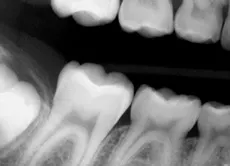

Digital sensors have many advantages over traditional X-ray film. One of the downsides is the lack of flexibility, which often results in an incorrectly positioned exposure, such as this example of a bitewing (Fig 1). If this is a challenge for you or you are looking for a time saving way to take X-rays, check out Flaps. Made of soft polyethylene, latex-free foam, they come in two sizes, original and long. Flaps can be used for horizontal or vertical bitewings and any periapical exposure. They accommodate all sizes of film and sensors — #0, #1, and #2.